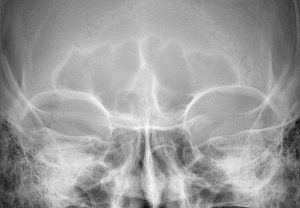

- CT imaging is often obtained preoperatively to assess sinus size and the thickness of the obverlying bone of the nedial brow prominences. The lateral or tail of the brow is always solid bone.